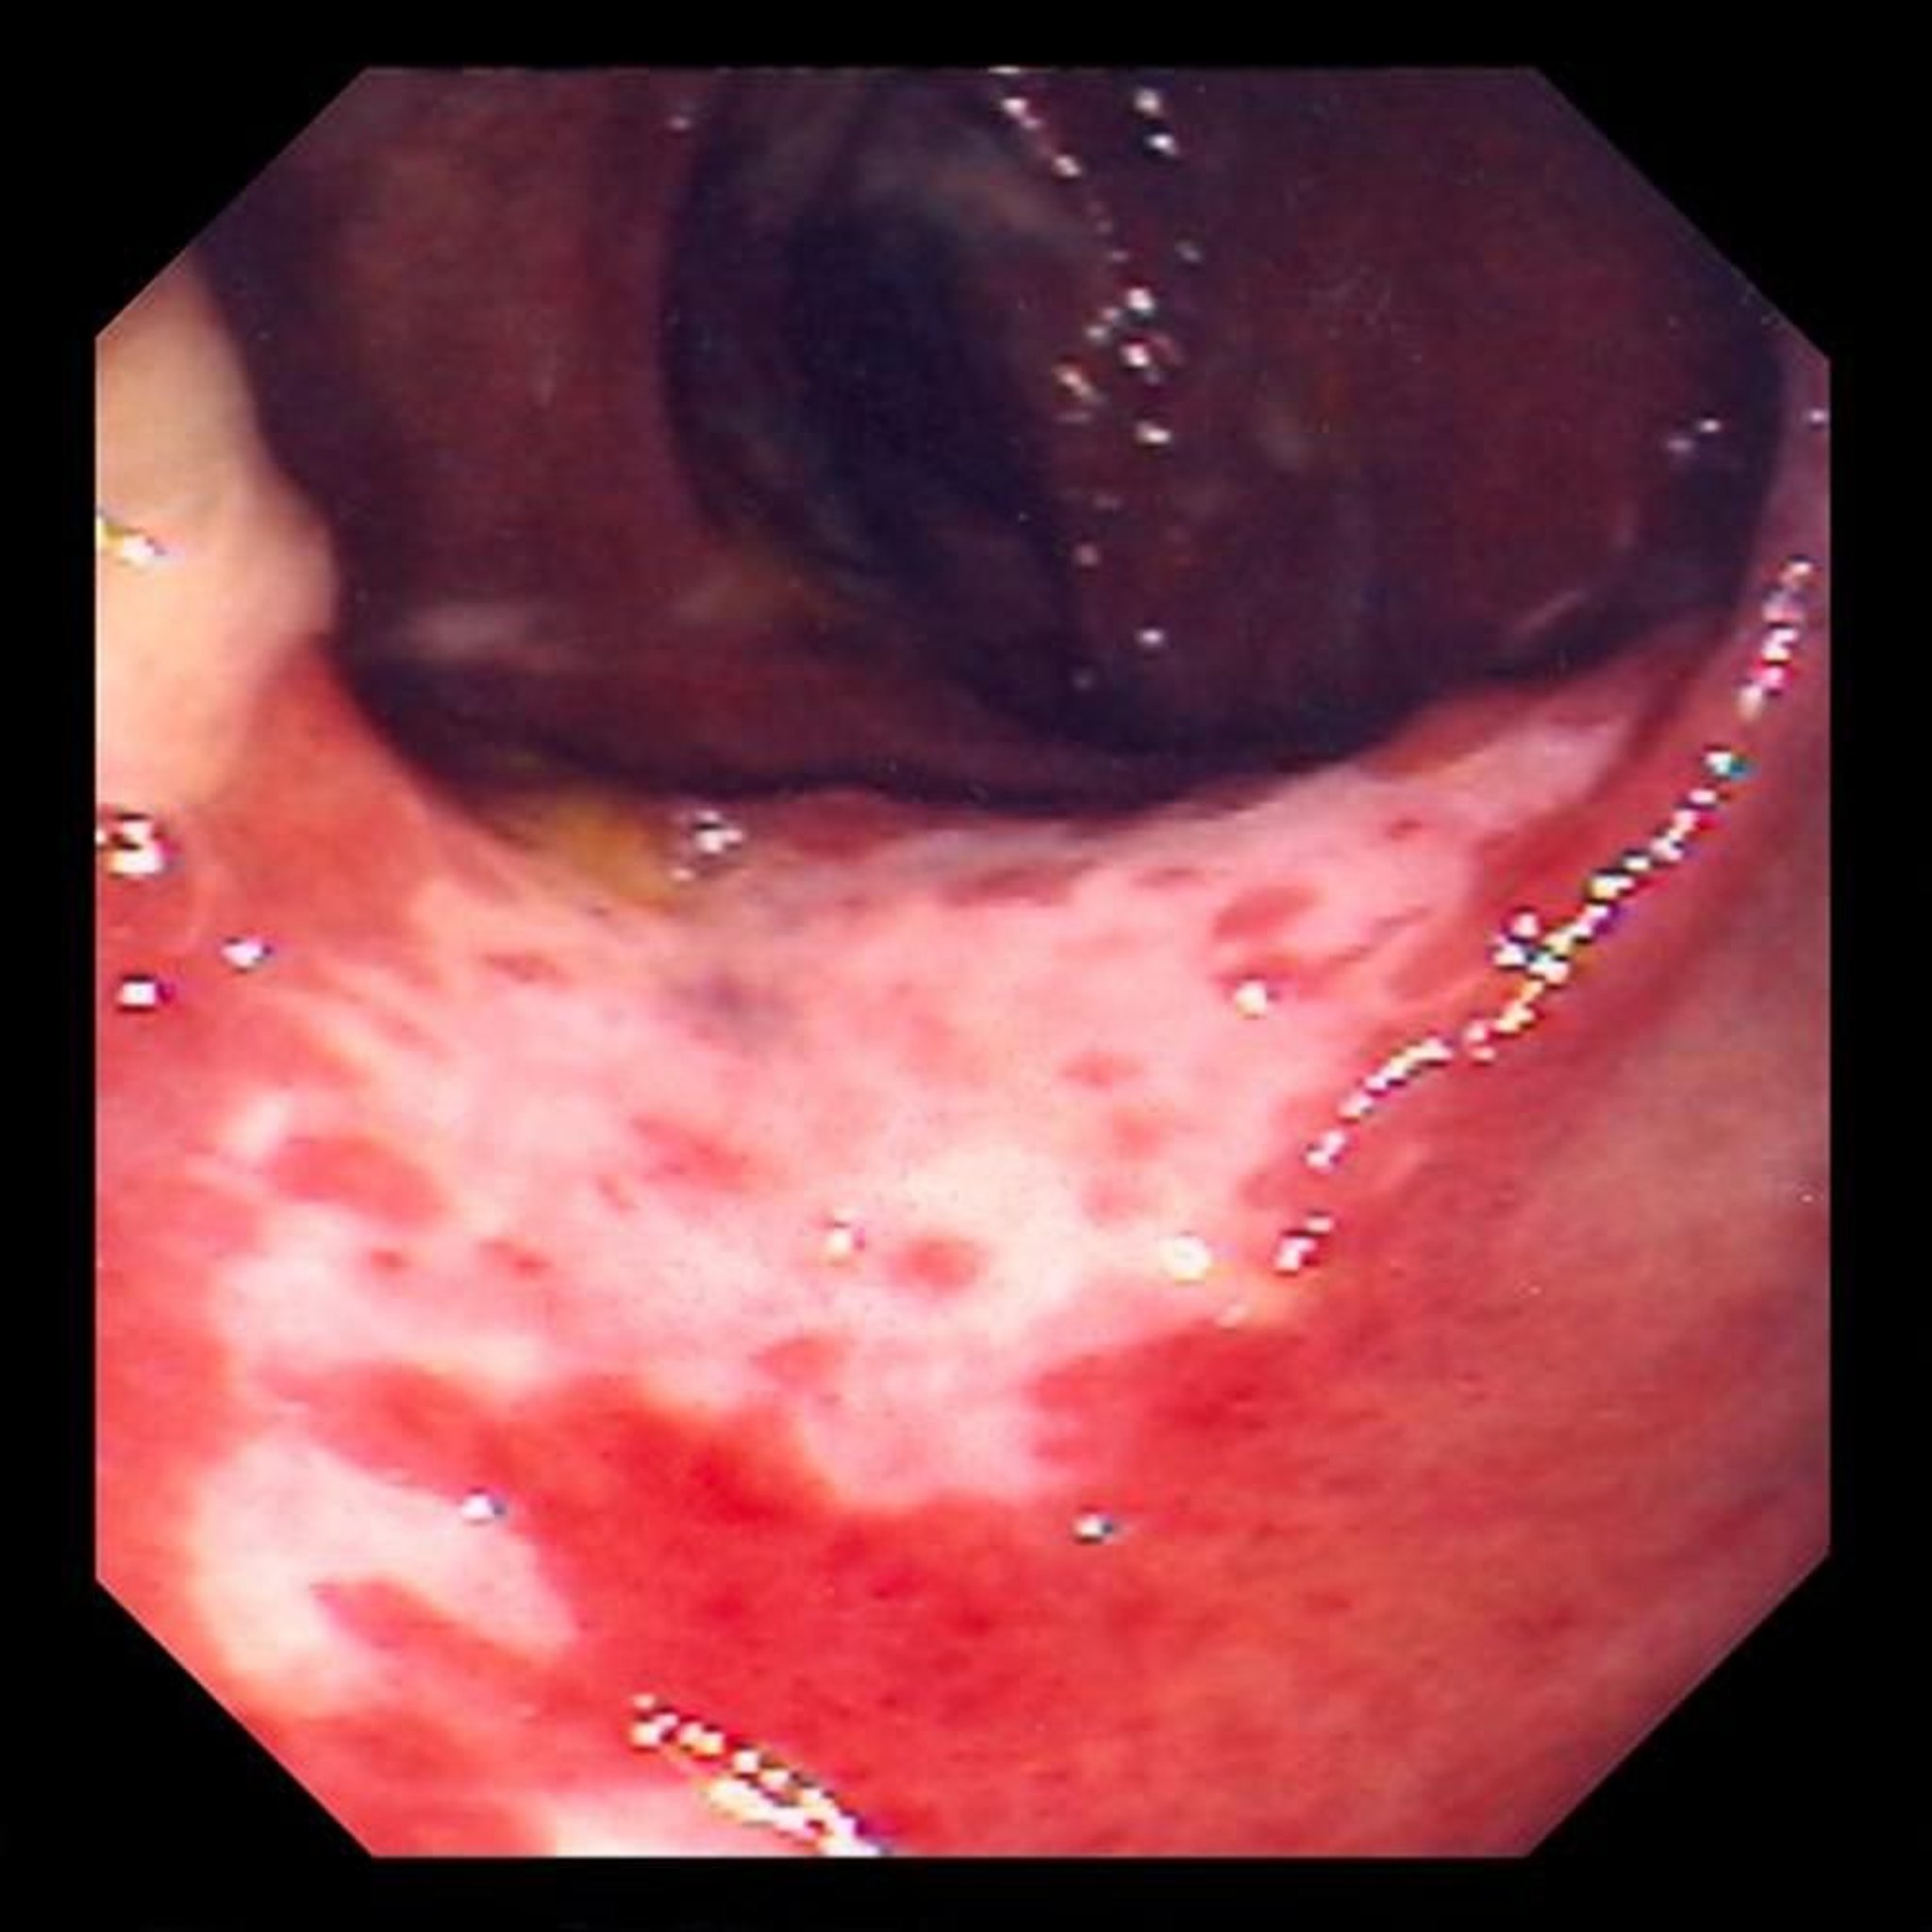

Colite isquêmica (colonoscopia)

Essa foto mostra lesões no revestimento do intestino causadas pelo bloqueio de fluxo sanguíneo. O revestimento do intestino é vermelho e coberto por úlceras (as áreas brancas).

Fotografia fornecida pelo Dr. David M. Martin.